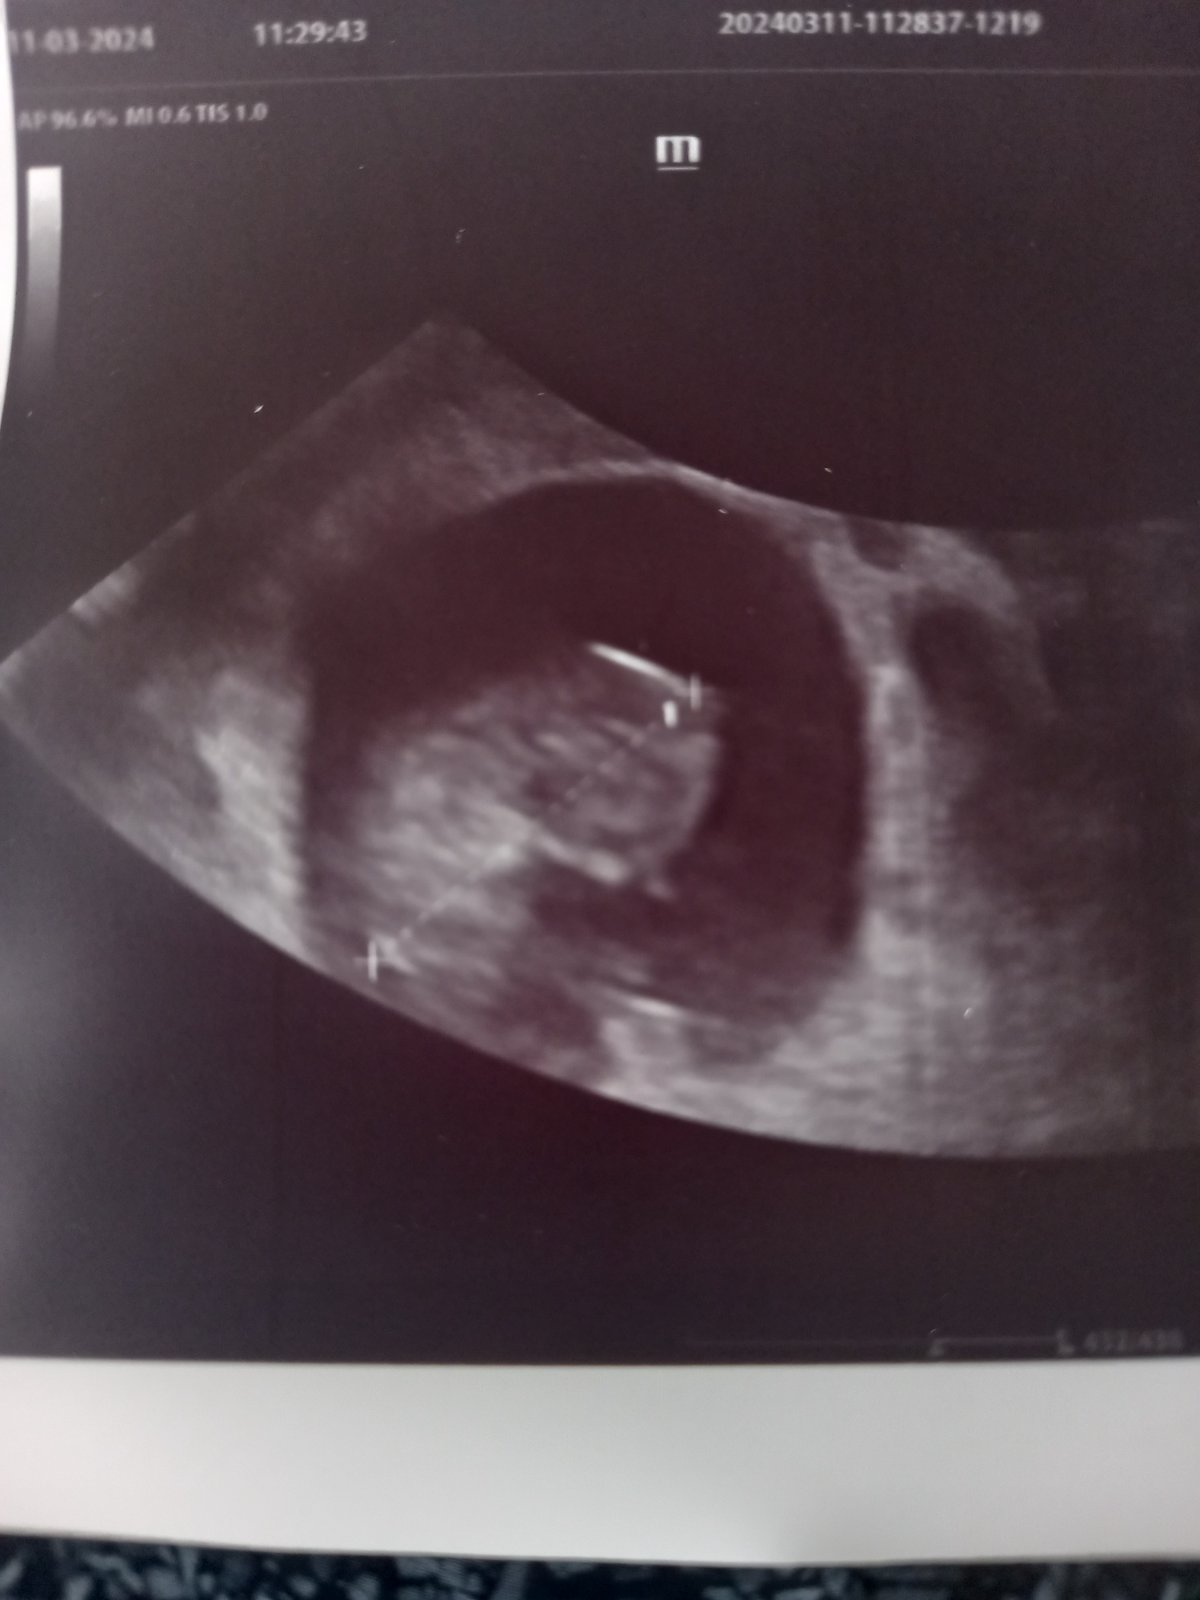

@aquenka já jsem byla dneska na kontrole a všechny bylo v pořádku 🍀 dostala jsem i fotečku